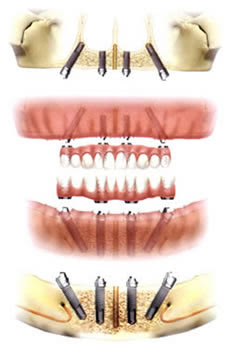

インプラント治療は、1本の人工歯を装着するために、あごの骨に一か所穴をあけ、そこにボルトのようなもの(インプラント)を埋め込みます。これが、歯を支える骨の代わりをしてくれるのです。埋め込んだインプラントに、人工の歯をしっかりと固定するというのがインプラント治療の流れです。2本人工の歯を固定するなら2本のインプラント、3本なら3本と、人工の歯をつける本数と同じ数のインプラントをあごの骨に埋めていくことになります。上あごだけ総人工歯にしようと思うと、実に14本ものインプラントをあごの骨に埋めることになるのです。

一方、オールオン4では、あごの骨にインプラントを埋めるところはインプラント治療と同じです。しかし、1本の人工の歯に対して1本のインプラントというわけではなく、上あごすべての歯を人工の歯にする際は4本、上下どちらも総人工歯にするなら上4本、下4本の合計8本のインプラントを埋めるだけでOKです。オールオン4は、1本のインプラントで1本の人工はを支えるというものではなく、4本のインプラントで片あごに必要な14本の歯を支えてしまう治療法なのです。

4本のインプラントで片あごに必要な14本の歯を支える、とご説明しましたが、具体的にどういうことなのかというと、4本のインプラントに、14本の人工歯をしっかりと支えてくれるフレームを装着して一体化させるということです。平たく言えば、歯ぐきのようなものですね。インプラントとフレームを一体化させることで、入れ歯のように何かのひょうしにずれることもなく、噛んだときや食いしばったときに力が均等に伝わり、硬いものでもしっかりと噛むことができます。また、かたよった力の入れ方から肩が凝ったり頭痛を起こしていたかたは、力が均等に入り、一部の歯に大きな負担がかかるということもないので、肩こりや頭痛の解消にもつながります。